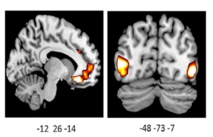

La imagen muestra una actividad incrementada en los cerebros de los portadores de la variante por delación del gen ADRA2b. Fuente: UBC.

El estudio, publicado recientemente en The Journal of Neuroscience, reveló que los portadores de una determinada variación genética percibían imágenes positivas y negativas con mayor intensidad, y presentaban una actividad cerebral aumentada en ciertas regiones del cerebro ante dichas imágenes.

El presente estudio, por su parte, es el primero que utiliza imágenes del cerebro para averiguar cómo este gen afecta a la forma en que la gente percibe vívidamente el mundo que le rodea. Incluso para Todd, los resultados han sido sorprendentes.

El estudio, publicado recientemente en The Journal of Neuroscience, reveló que los portadores de una determinada variación genética percibían imágenes positivas y negativas con mayor intensidad, y presentaban una actividad cerebral aumentada en ciertas regiones del cerebro ante dichas imágenes.

La investigadora analizó los cerebros de 39 participantes, 21 de los cuales eran portadores de la variación genética.

De todos los voluntiarios, los portadores de dicha variación mostraron significativamente más actividad en una región del cerebro responsable de la regulación de las emociones, y de la evaluación tanto del placer como de la amenaza.

La investigadora analizó los cerebros de 39 participantes, 21 de los cuales eran portadores de la variación genética.

De todos los voluntiarios, los portadores de dicha variación mostraron significativamente más actividad en una región del cerebro responsable de la regulación de las emociones, y de la evaluación tanto del placer como de la amenaza.